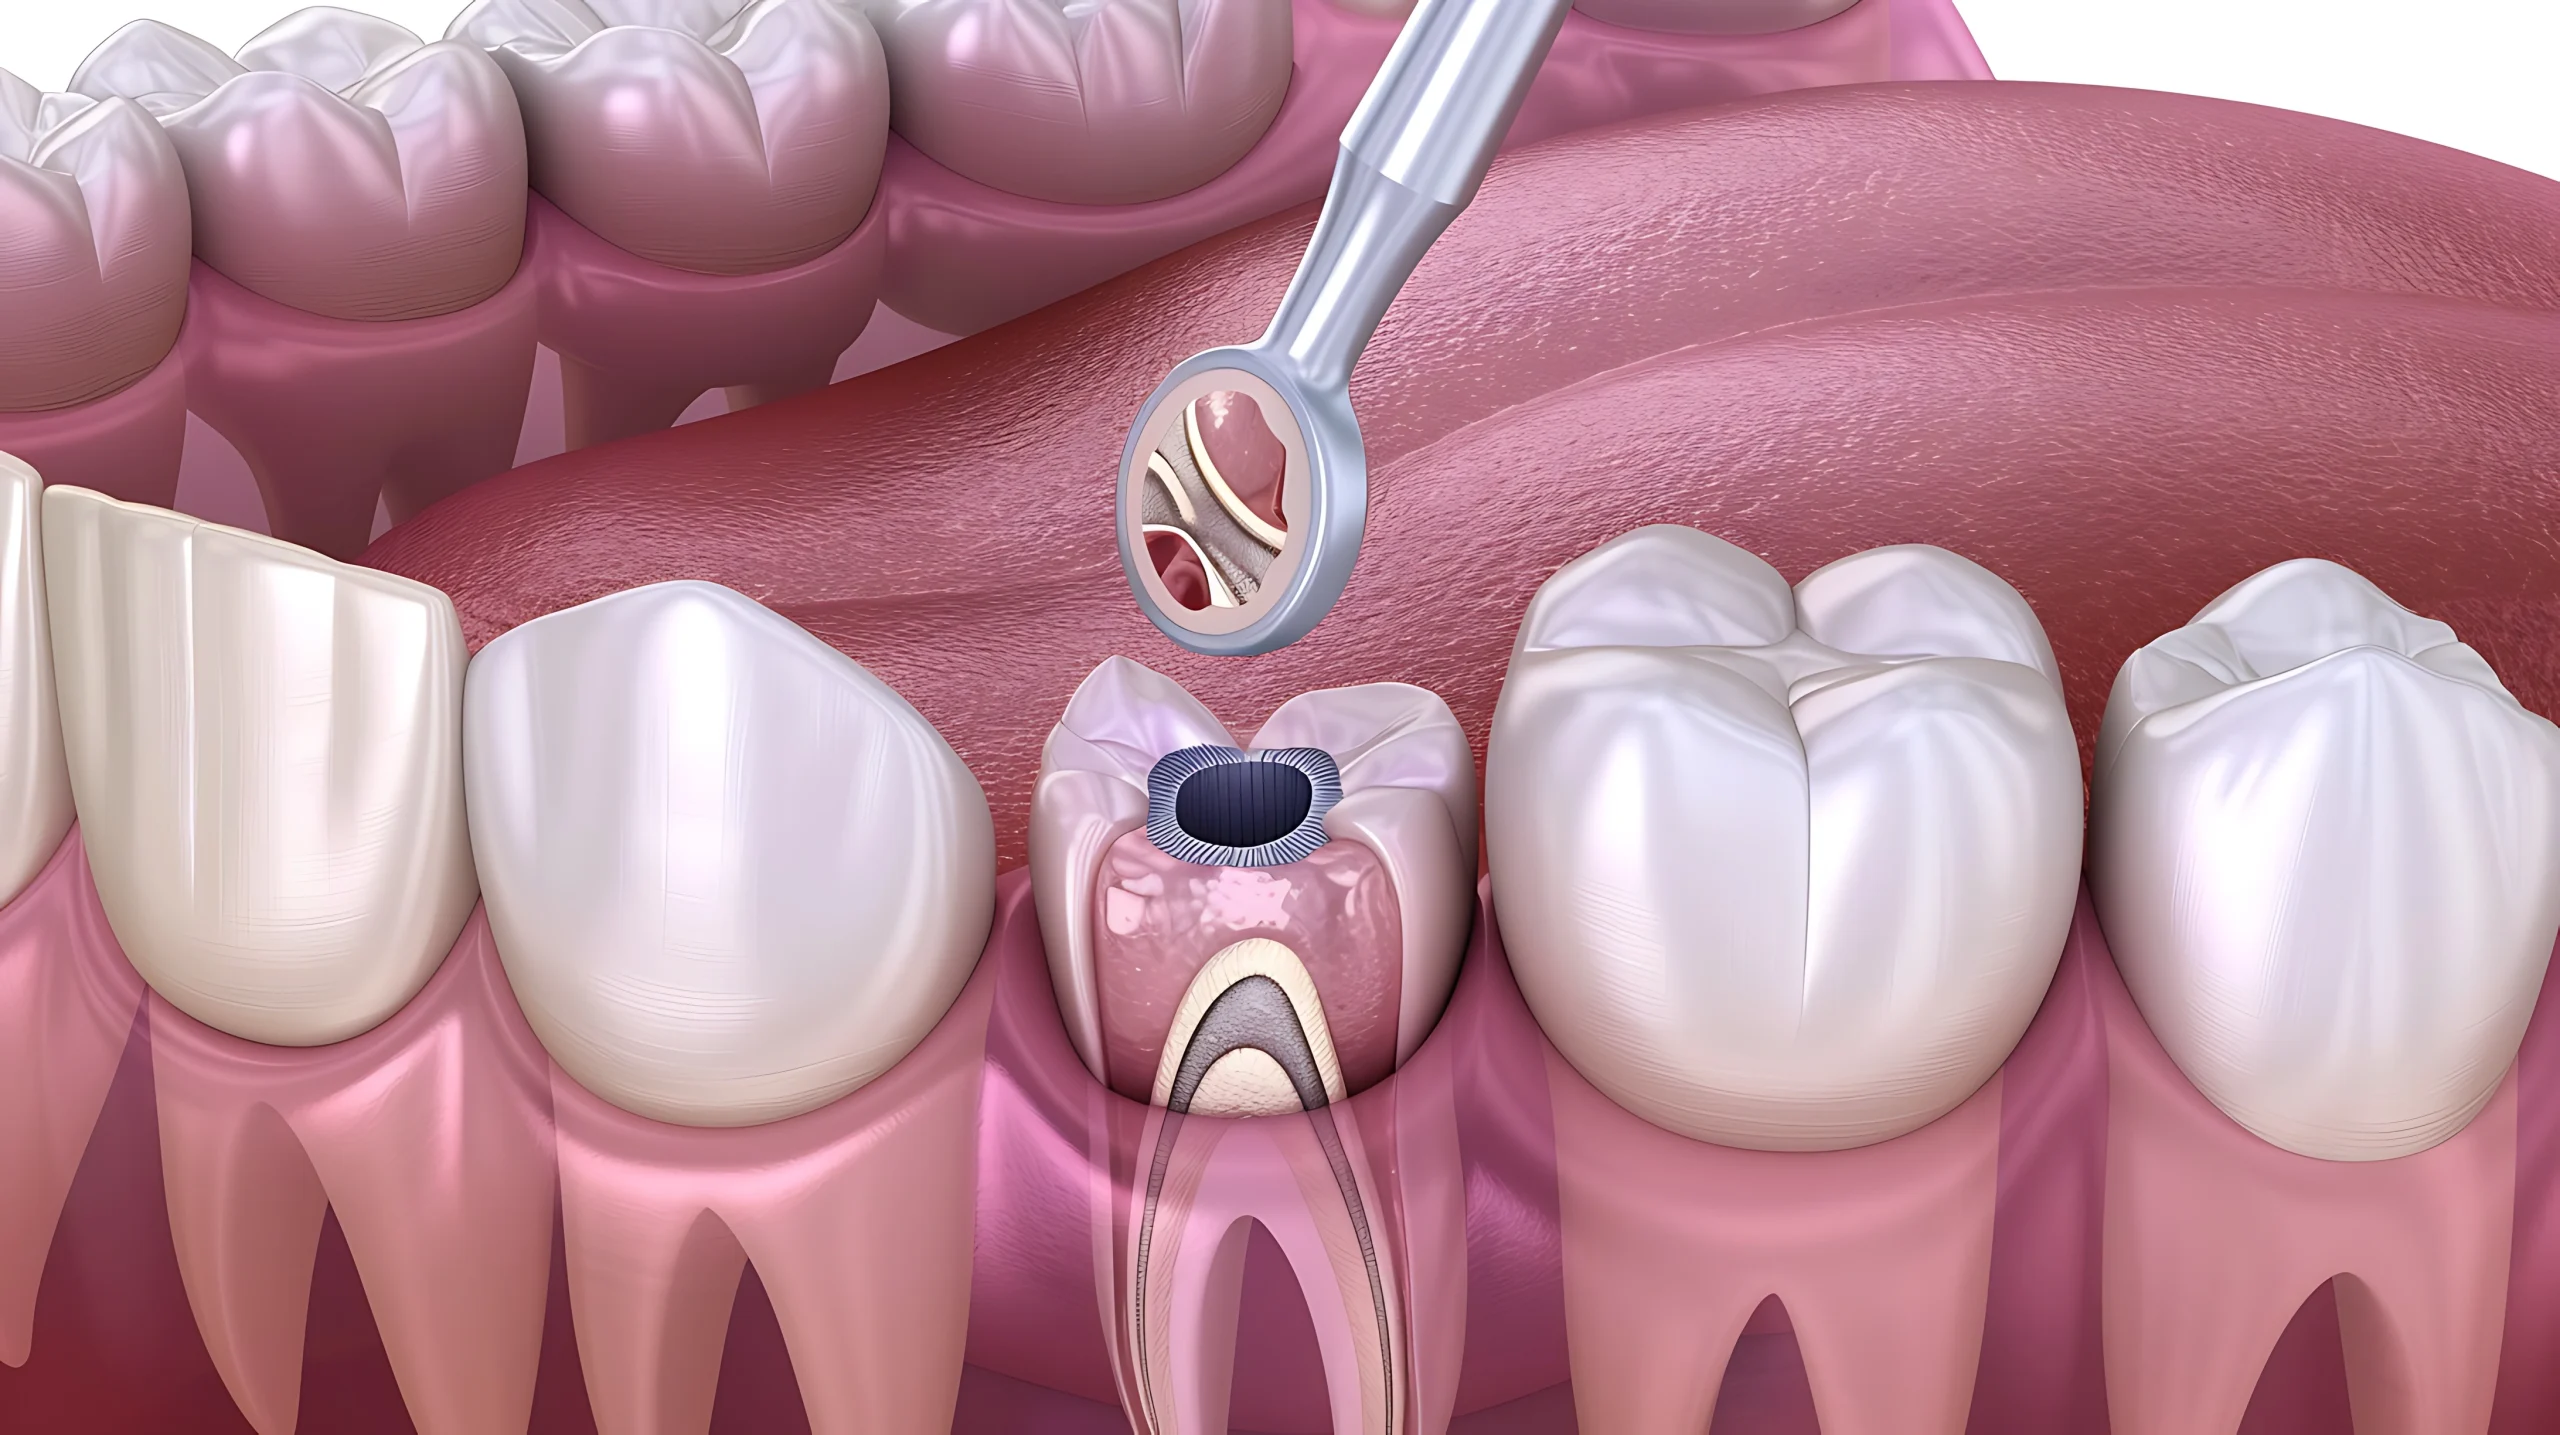

A root canal is needed when decay, injury, or infection reaches the tooth’s inner pulp, causing pain, sensitivity, or swelling. The infected tissue is removed, the canals are thoroughly cleaned, disinfected, and sealed, and the tooth is later strengthened with a crown to restore full function.

A root canal works by eliminating infection from inside the tooth and protecting it from recurring damage.

Digital X-rays help determine the exact depth of the canals, while rotary endodontic tools ensure precise cleaning and shaping. Once disinfected, the canals are tightly sealed to block bacteria. Finally, a crown reinforces the tooth for durability, restoring natural function and appearance.

The infected or damaged pulp is carefully removed to stop the source of pain and infection.

The canals are disinfected and shaped with rotary tools for accurate sealing and long-term success.

A biocompatible material is placed inside the canals to prevent reinfection and protect the tooth from within.

A crown is placed to restore strength, chewing function, and natural appearance.